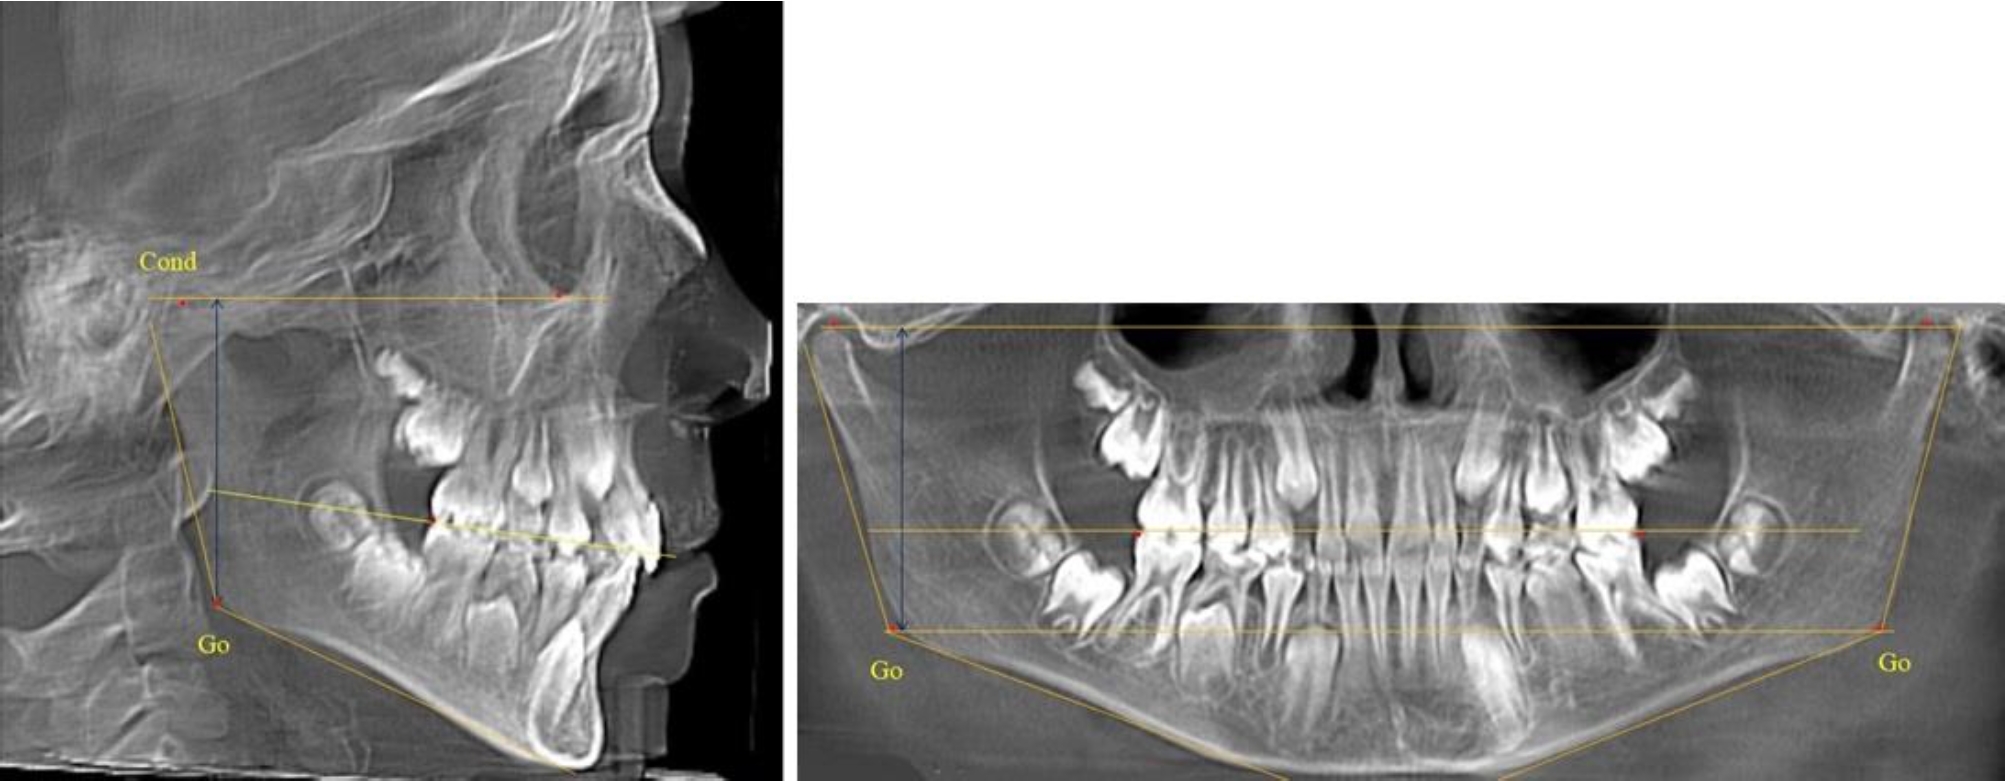

В 4-й группе были проанализированы 12 комплектов рентгенограмм, что составило (11,32 ± 3,08) % от общего числа. На всех рентгенограммах произошла полная смена всех молочных зубов постоянными. Окклюзионная линия делила ветвь на два отдела (рис. 4).

Рис. 4. ТРГ пациента после смены всех молочных резцов

Высота ветви у детей 4-й группы составляла (54,27 ± 2,59) мм, что было достоверно больше, чем у детей 1-й группы (р ˂ 0,05). При этом высота верхней окклюзионно-суставной части была (32,51 ± 1,72) мм, а нижней – (21,76 ± 1,42) мм. Высота верхней части была больше нижней, что и определяло особенности соразмерности частей ветви нижней челюсти в анализируемый возрастной период.

Относительные показатели соразмерности частей ветви нижней челюсти показали, что отношение высоты верхней части ветви к нижней в среднем составляло 1,49 ± 0,12. Отношение общей высоты ветви к верхней ее части составляло 1,67 ± 0,14, а отношение общей высоты ветви к нижней ее части было 2,49 ± 0,15, что и определяло особенности соразмерности частей ветви нижней челюсти в анализируемый возрастной период.